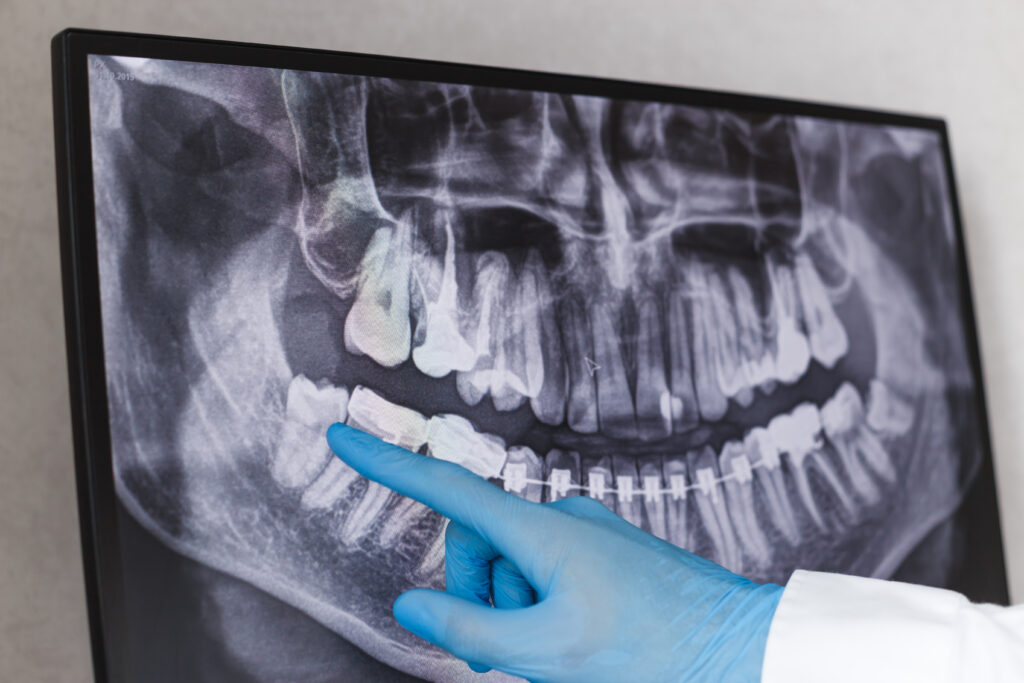

Dr. Long performs a detailed examination including 3D imaging to assess the position of your wisdom teeth, their relationship to adjacent teeth and nerves, and whether removal is recommended. This thorough evaluation determines the complexity of extraction and helps plan the safest approach for your specific situation.

Impacted wisdom teeth can develop cysts or tumors around them, which can damage your jawbone and adjacent teeth. Regular monitoring through X-rays helps identify developing cysts early, and removal of the wisdom tooth eliminates the risk of continued cyst growth.